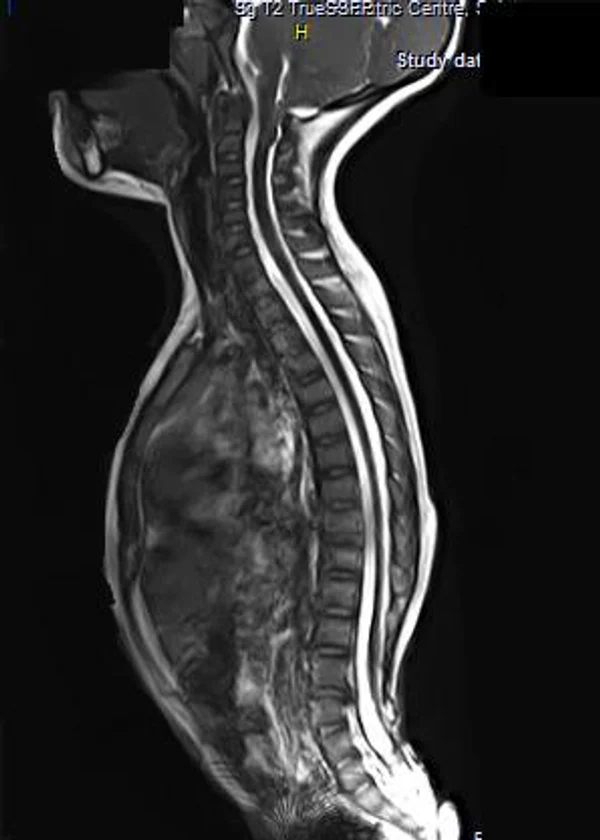

Spina bifida, спинно-мозговые грыжи, диастематомиелия, липоменингомиелолоцеле, фиксированный спинной мозгSpina bifida включают различные типы нарушения закладки и развития нервной трубки на спинальном уровне, что сопровождается незаращением дужек позвоночника и часто сопровождается одновременным пороком развития спинного мозга и его оболочек. Встречаются у 1 на 1000 – 3000 новорожденных. Могут наблюдаться в различных отделах позвоночника, но наиболее часто встречается в пояснично-крестцовом отделе. Незаращение дужек позвонков с наличием грыжевого выпячивания обозначается в литературе по разному: спинно-мозговые грыжи, spina bifida, spina bifida cystica, spina bifida vera, spina bifida typica, spina bifida aperta. Классификация spina bifida aperta: I Рахишизис. II Спинномозговые грыжи. Менингоцеле. Менингорадикулоцеле. Миеломенингоцеле. Миелоцистоцеле. Липоменингомиелоцеле. Основные сопутствующие пороки центральной нервной системы: Гидроцефалия до 65-85%. Аномалия Киари 2. Сирингомиелия.